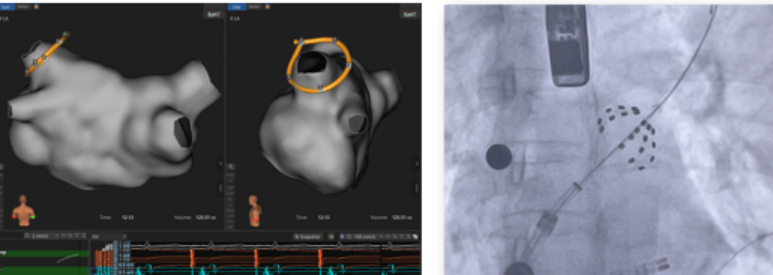

PFA手术通常在全身麻醉下进行,术中需持续监测心电图、血压、血氧饱和度及体温变化。由于PFA依赖精确的电场分布,导管定位至关重要。推荐采用三维电解剖标测系统辅助,确保消融线完整覆盖肺静脉口部。

图2、二维三维相结合

术中应严格控制能量参数,避免过度消融导致局部组织坏死或微小血管破裂。同时注意观察是否有异常心律、低血压或心包填塞征象。一旦发现异常,应立即停止操作并采取相应措施。